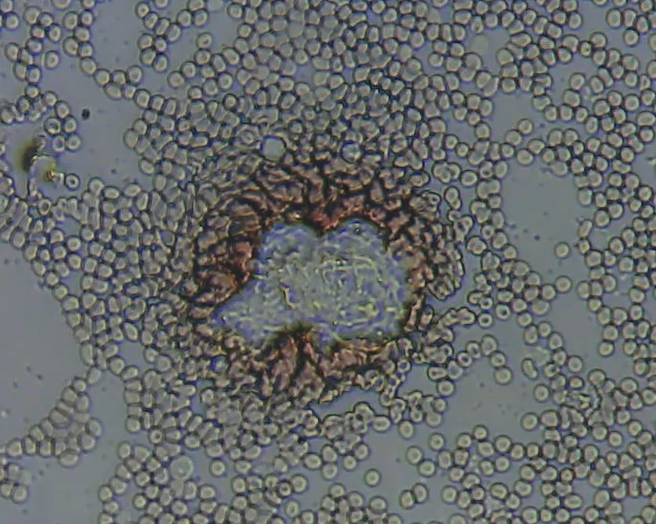

実際には、血液中の分子の細部まで光学顕微鏡で見ることはできません。見えるのは血漿と、血漿に多少溶解したコレステロールなどの分子の塊だけです。血液中に見られる濃縮された分子やクラスターは、異物である可能性があります。

血液中の異物の一例は、これです。私のイメージです。